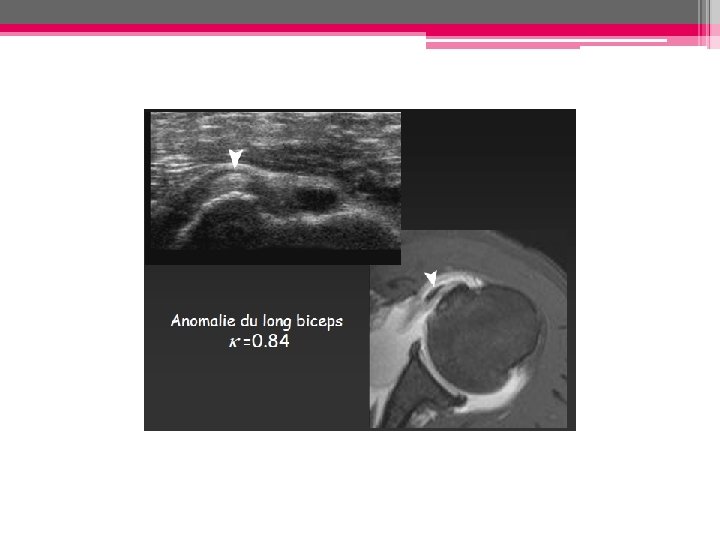

¤ Tendinose bicipitale: • Anomalies morphologiques du tendon: épaississement, amincissement ou irrégularités de ses contours Si épaissi, caractère arrondi (et non plus ovalaire) du tendon en coupe transversale+++ • Anomalies de son échostructure: aspect hétérogène ou globalement hypoéchogène • IRM: augmentation du signal du tendon en T 1 et T 2 (image piège T 1 et DP: angle magique) ¤ Fissuration tendineuse: = défect intratendineux hypoéchogène en échographie, hyperintense T 2 en IRM et rempli par le PDC en arthro-scanner et arthro-IRM